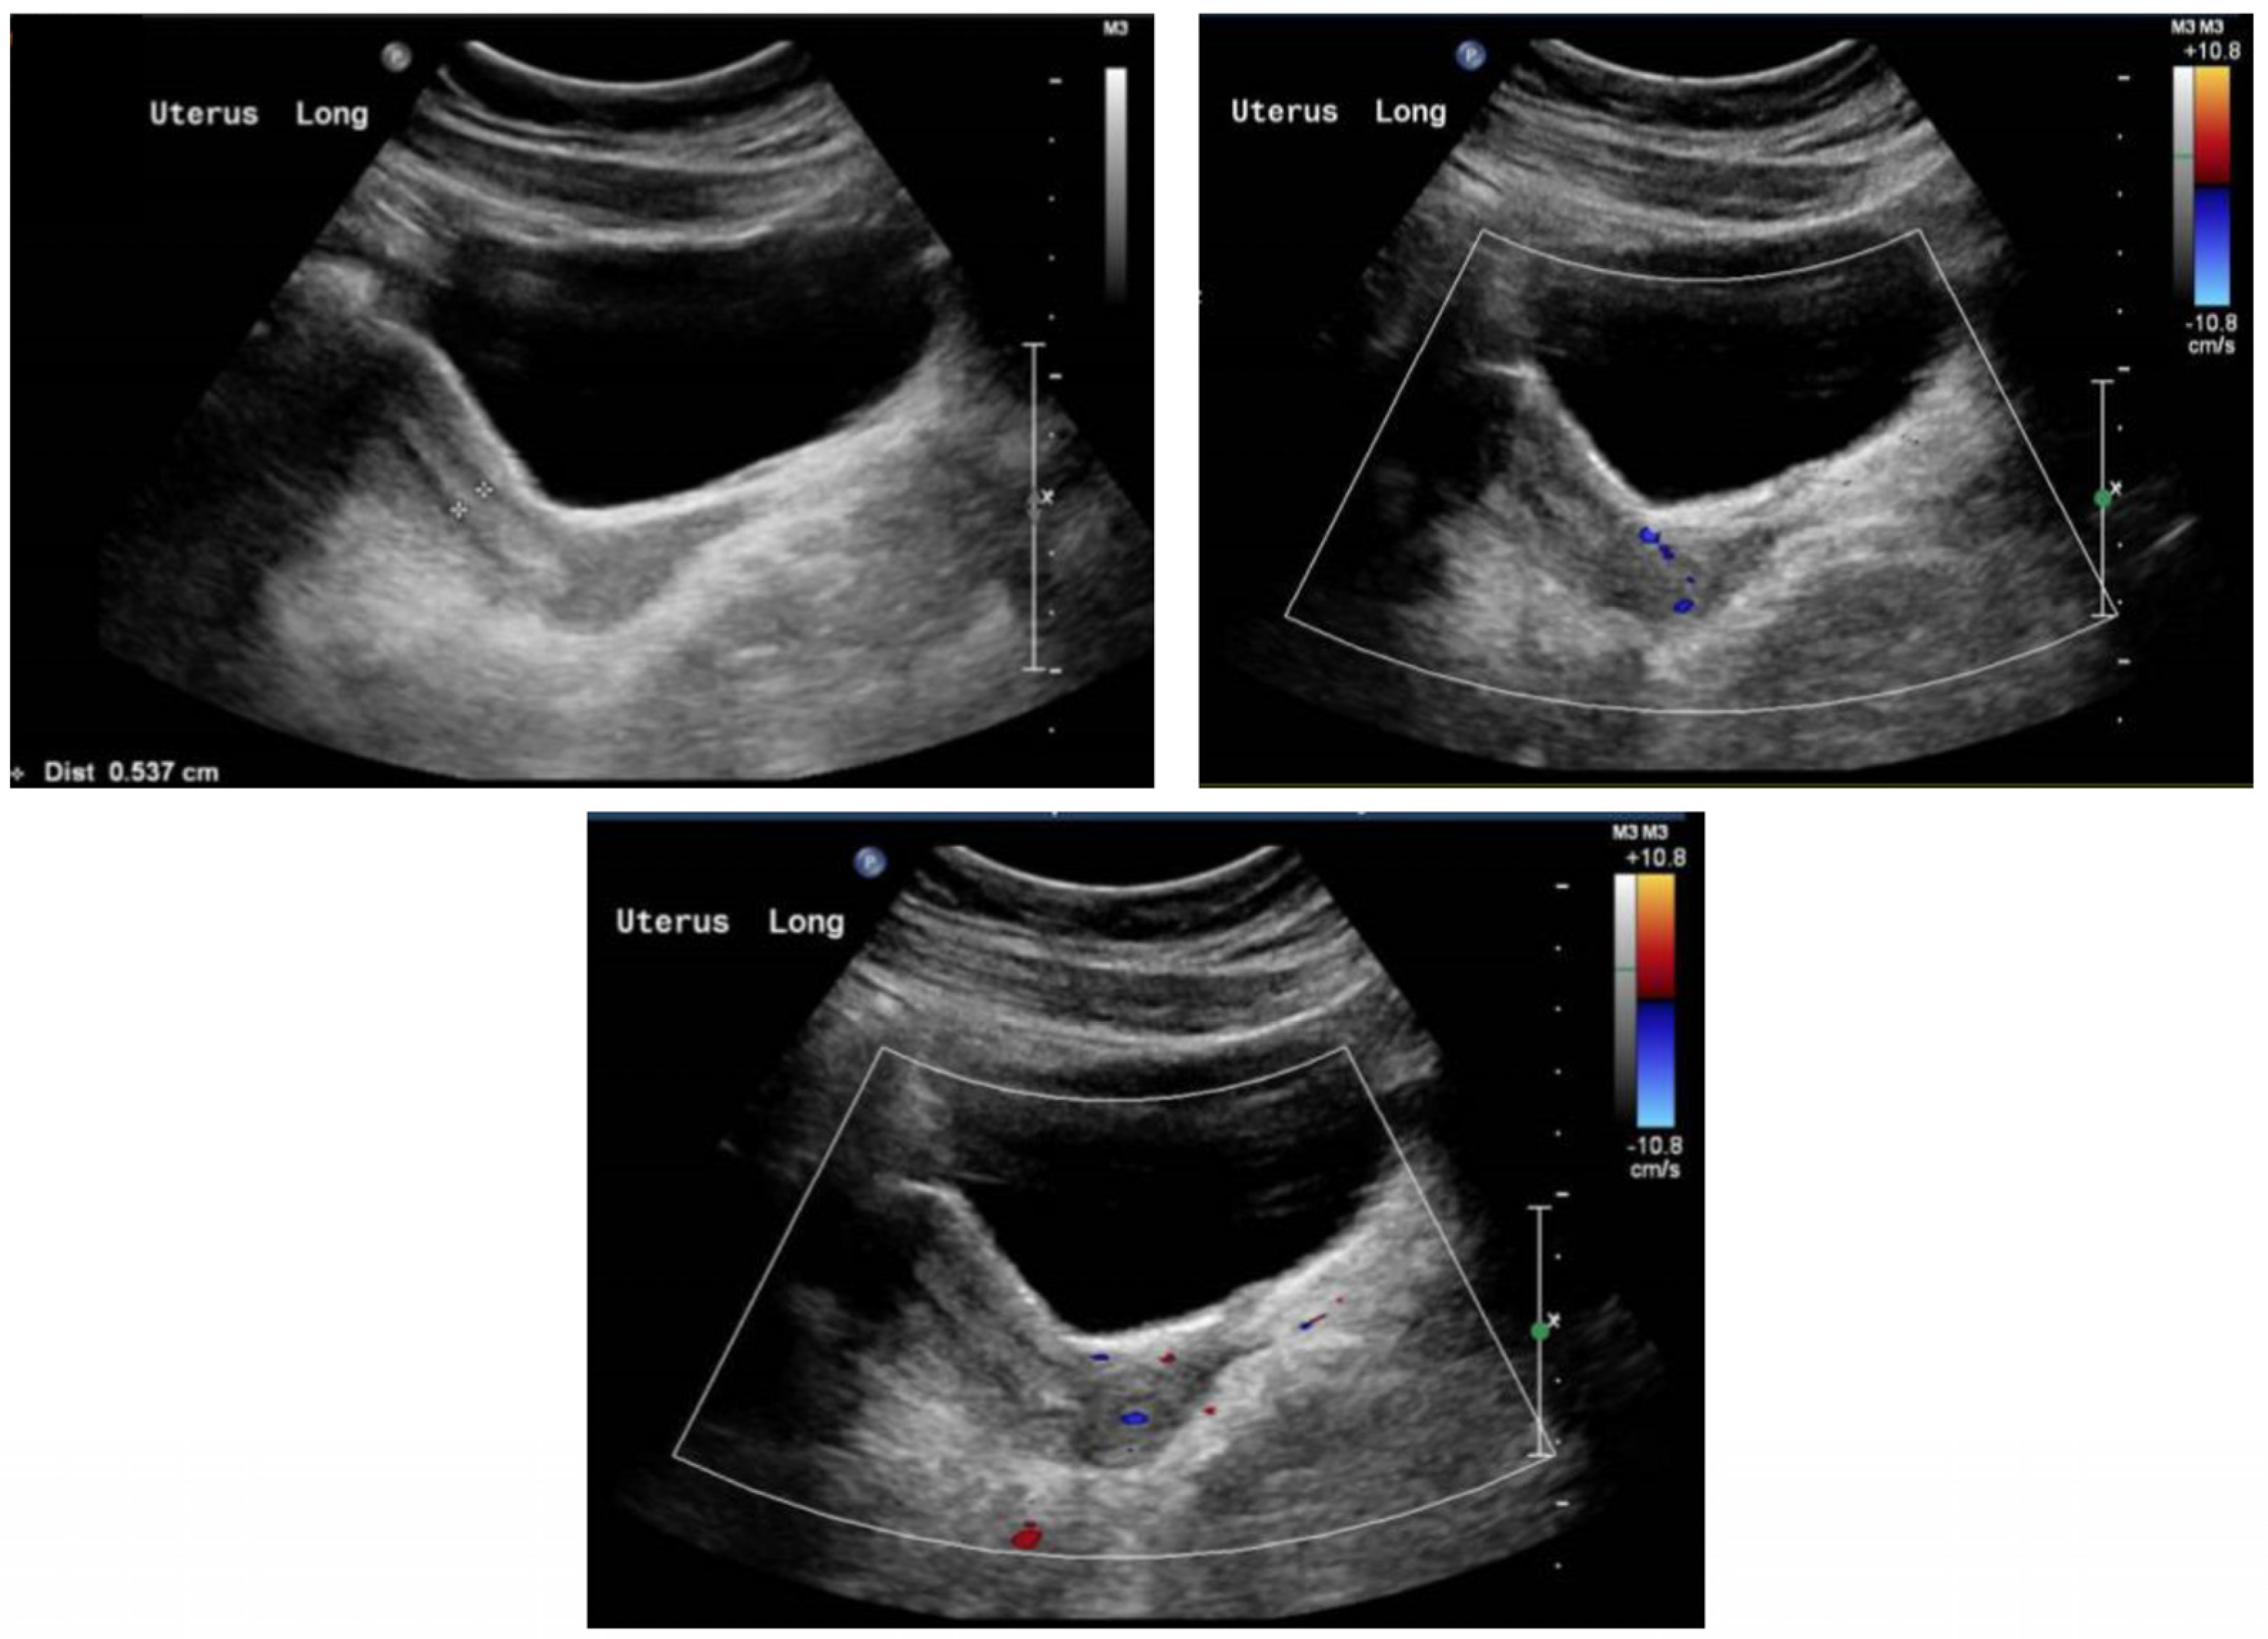

2. Case Report